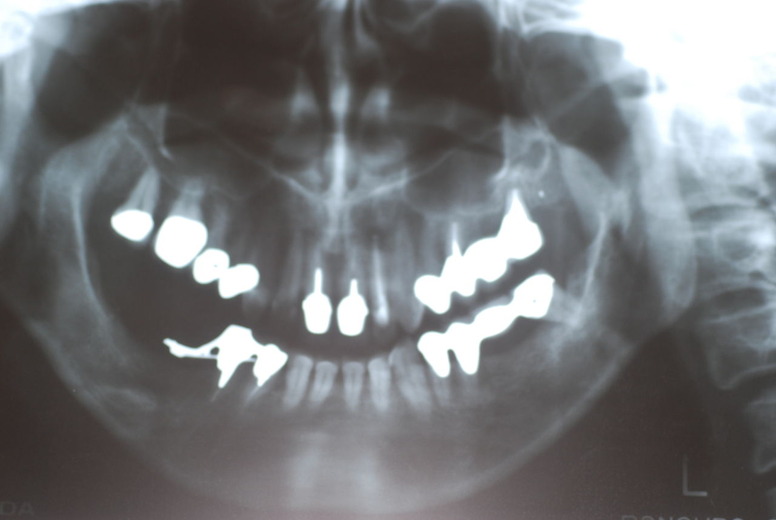

親知らずを取ることを嫌がる方が多いのですが、もし親知らずとその隣の14歳大臼歯の間に虫歯ができたり歯周病を罹患した場合、どれほど治療が大変で再発も起こりやすいか理解できない方がおおいのです。

写真左下の親知らずが痛くなり抜歯しました。その後歯茎を除去して虫歯を露出させる処置を二回ほどしています。

レントゲンでは小さいですが、こう言う虫歯が一番怖いのです。

治療の成功率は極めて悪くすぐ再発しやすいのです。